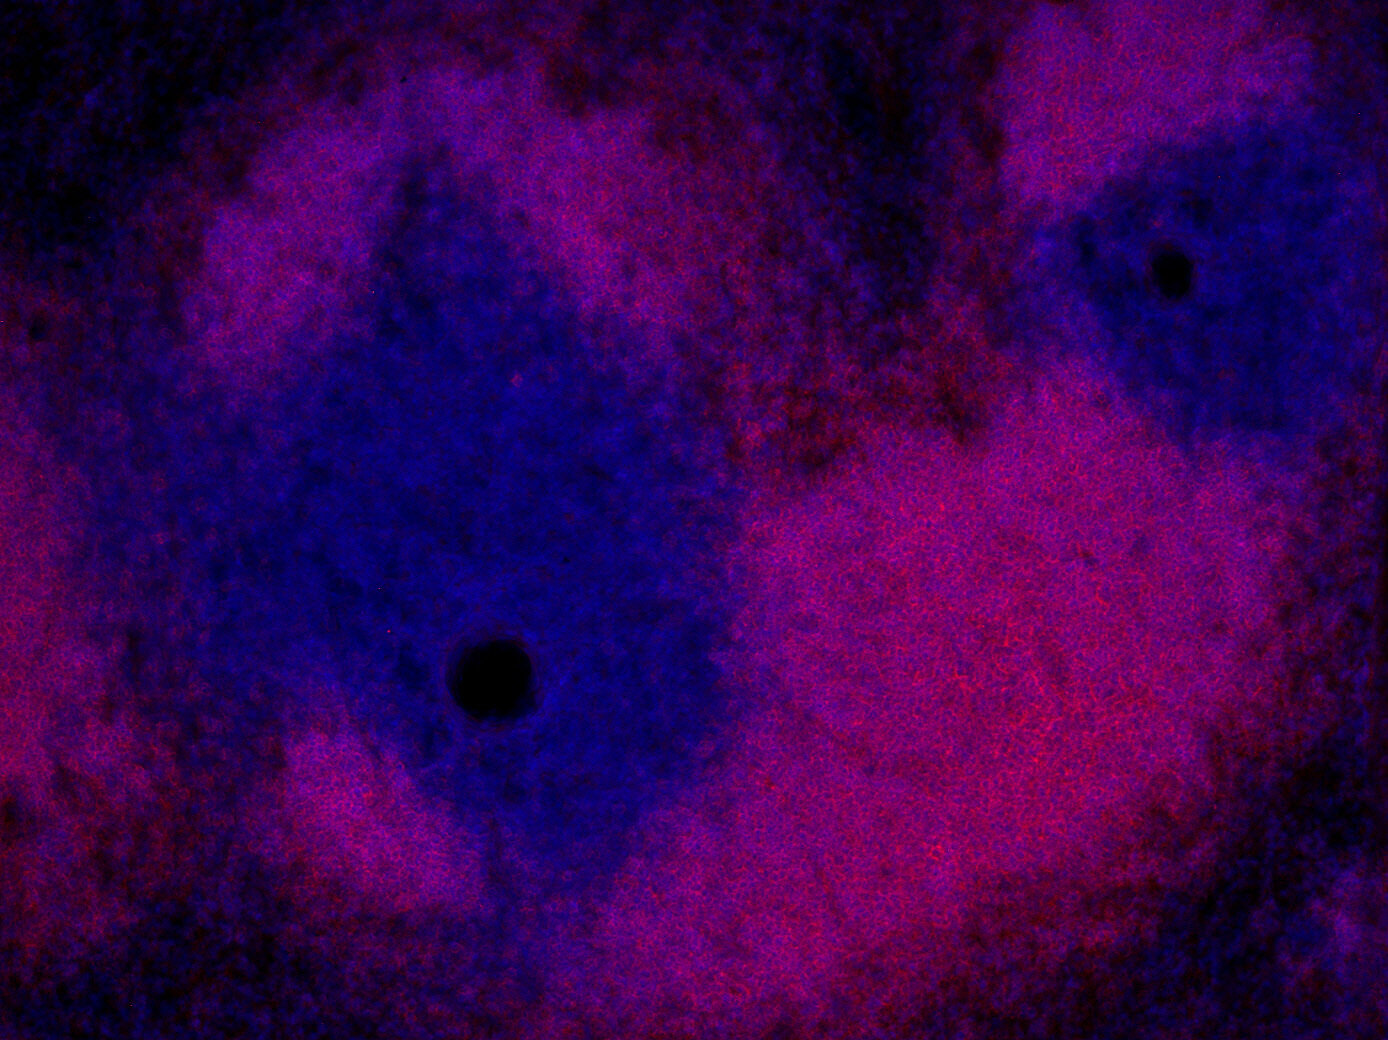

IHC: 1 : 500 gallery

Immunohistochemistry (IHC) on 4% PFA perfusion fixed tissue with 24h PFA post fixation. Immunoreactivity is usually revealed by fluorescence or a chromogenic substrate. Some antibodies require special fixation methods or antigen retrieval steps. For details, please refer to the ”Remarks” section.